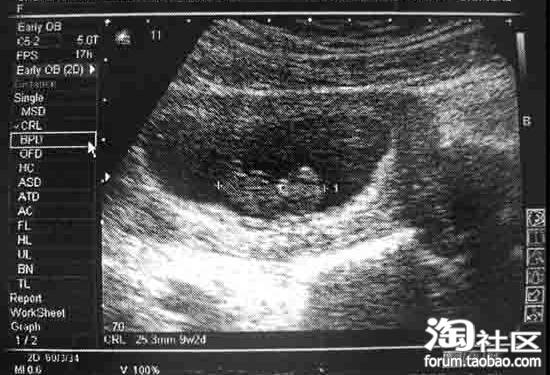

上周去检查了,回来非常难过。大夫建议再看看,如果是母体的原因,这个宝宝还有希望,如果是胚胎的事,便要采取刮宫流产了……刮宫流产至少也要半年以后再能再要孩子,朋友还告诉我,做刮宫,疼不用说了,搞不好连以后再要小孩的机会都没了。55555555555555555,太伤心了……昨天我哭了好久呢。